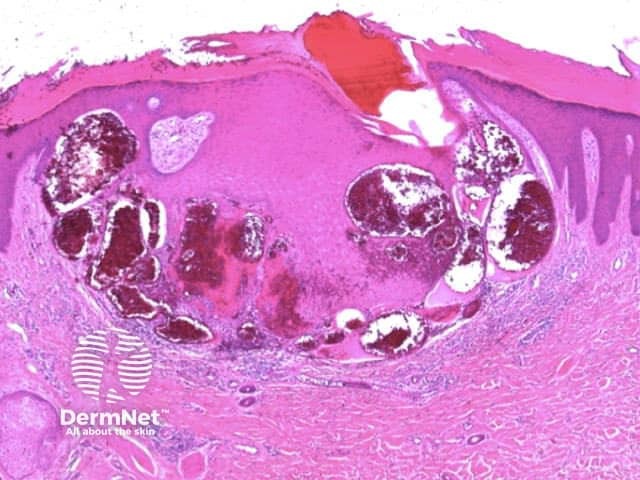

Clods are solid rounded structures of sufficient size to show an appreciable variability in size. Their colour depends on the nature and, in the case of melanin, depth of the substance they comprise (Figures 37-50). Other terms have been used for clods in specific settings such as blue-grey ovoid nests for grey and / or blue clods seen in basal cell carcinoma.

Figure 48. Diagram. Brown, grey and blue clods are due to nests of melanin-containing cells at different levels in the skin. From Kittler et al (1).